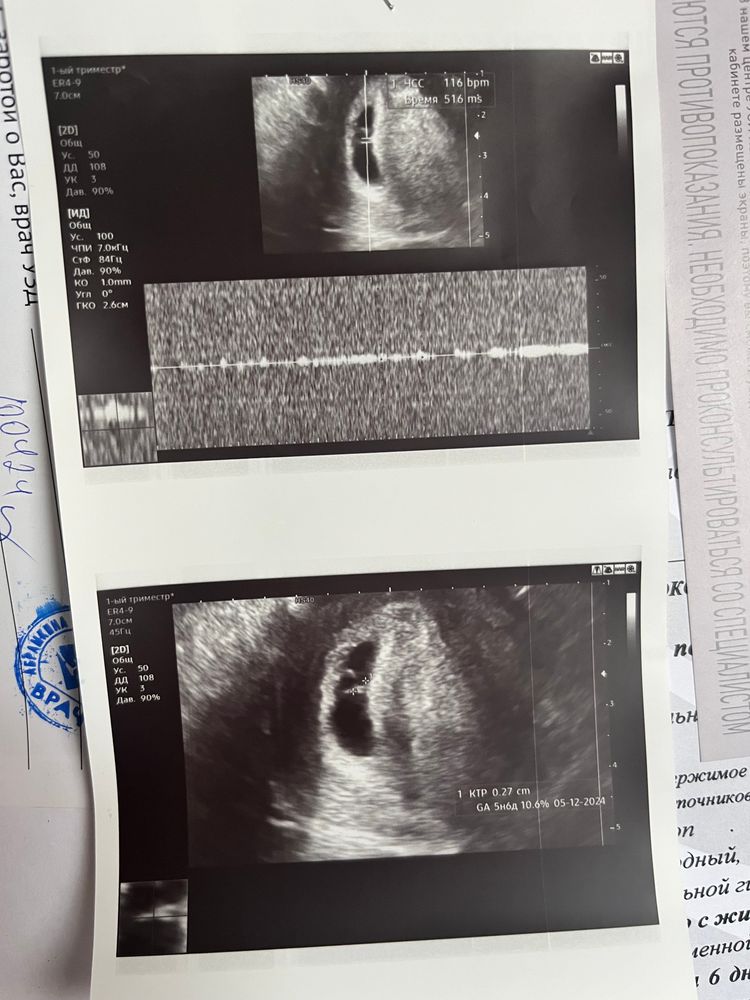

Натали в ЭКО-мама 2 года Первое УЗИ 21 ДПП Результаты УЗИ 💟 10.04.2024 💟 По УЗИ 5 нед. 6 дней ❤️ СБ 116 Посмотрите еще 20 записей на эту тему Лучший ответ Наталья Какое счастье !!! 🙏🙏🙏 Лёгкой вам и беременности 😇😇😇 22.04.2024 Ответить Натали Наталья , благодарю 🙏🏻🩷 22.04.2024 Ответить Отменить Ответить Леночка 👏🏻👏🏻👏🏻 теперь только расти и развиваться! 22.04.2024 Ответить Натали Леночка, спасибо 🩷 22.04.2024 Ответить Первый скрининг при ЭКО , риск 1:129 Долгожданное узи💜 Чаты Беременных Выберите чат: Январята-2026 Февралята-2026 Мартята-2026 Апрелята-2026 Майчата-2026 Июнята-2026 Июлята-2026 Августята-2026